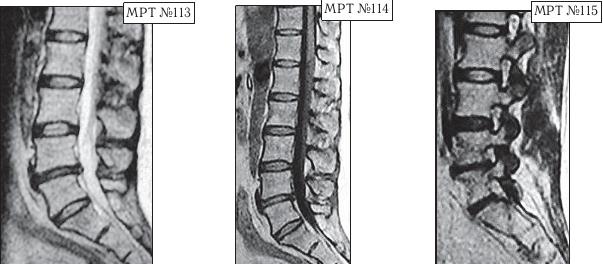

На протяжении последних десяти лет у пациентки периодически возникали боли в поясничном отделе позвоночника. Она к ним привыкла и не переживала по этому поводу, так как боли были умеренные, быстро проходили и довольно легко переносились. Но полтора года назад, после физической нагрузки, появились сильные, тянущие боли в ноге. Женщина вынуждена была обратиться в больницу по месту жительства. Пациентку направили к невропатологу, который, осмотрев её, сделал предположение, что возможно у неё «грыжа межпозвонкового диска» и направил женщину на МРТ.

Так вот, сделав МРТ (МРТ №№ 113–115), женщина вернулась со снимками к невропатологу. Он ознакомился с результатами обследования и вместо того чтобы назначить ей консервативные методы лечения при таком диагнозе, направил её… на консультацию к нейрохирургу. Нейрохирург между прочим специалист высокого класса, с большим опытом работы, спасший много человеческих жизней. Однако и он, ознакомившись с результатами обследования, осмотрев пациентку, сделал вывод, что необходима срочная операция по удалению грыжи межпозвонкового диска в сегменте LIV-LV.